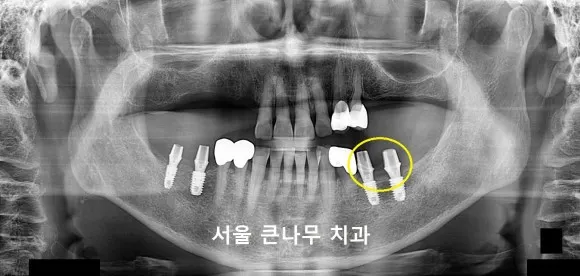

아랫부분의 경우에는 틀니 대신 임플란트를 심어 보충하였습니다.

양쪽 두 개씩 임플란트가 들어가게 되었고 임플란트 2개는 건강보험 혜택이 적용되기 때문에 비용이 절감되어 합리적인 가격에 진행하실 수 있었습니다.

2달의 시간이 지난 후 본격적인 보철이 들어가게 됩니다.

임플란트 기둥과 보철을 연결해 주는 나사를 연결해 주었습니다.

연결해 주는 나사를 지대주라고 부르는데요, 개인의 구강상태에 맞춰 제작이 가능합니다. 잇몸선에 맞춰서 만들어지기 때문에 맞춤지대주를 사용하여 제작될 경우, 보철이 더욱 편안하게 들어가게 됩니다.